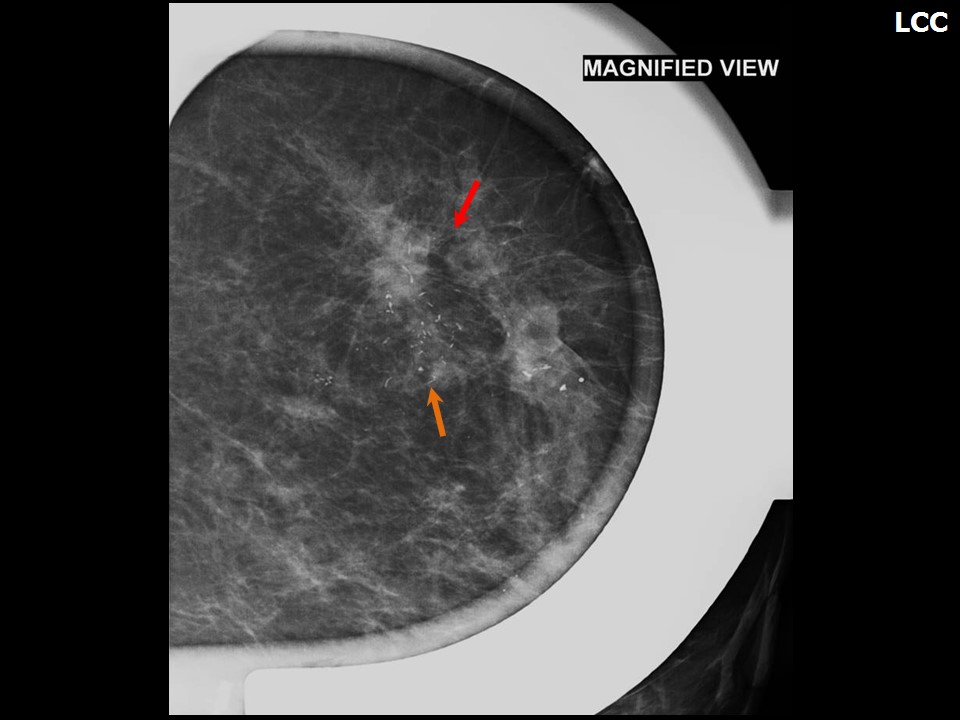

Феномен гипердиагностики в маммографии: примеры и иллюстрации

Раздел: Образы вокруг